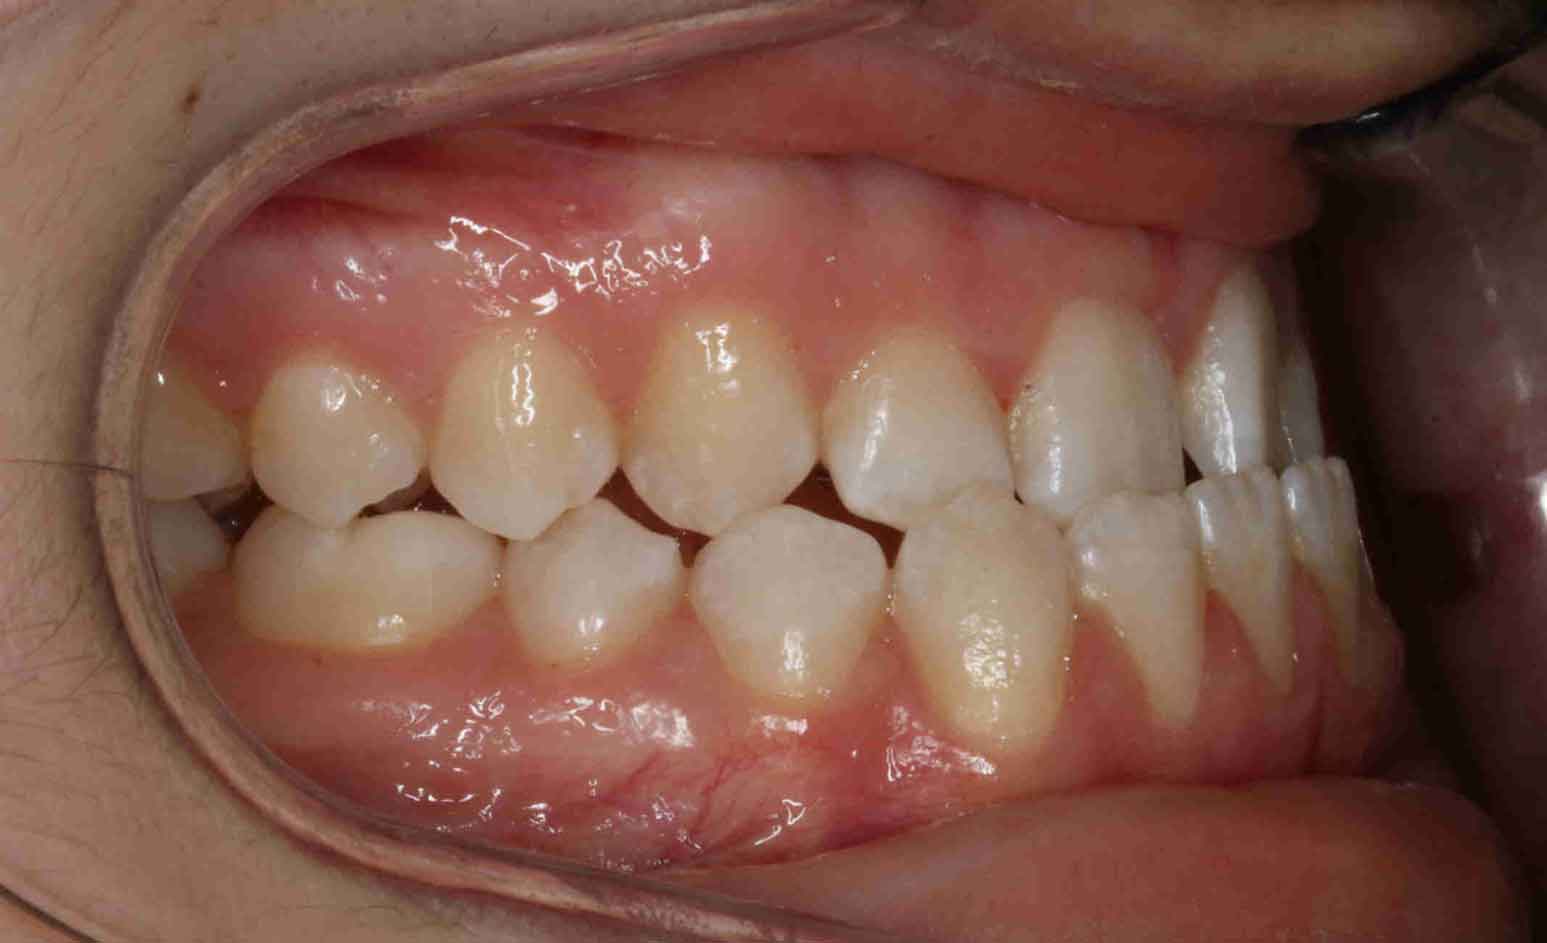

Clases III

En las siguientes imágenes puedes ver distintos resultados del tratamiento, deslizando la barra central de un lado a otro.